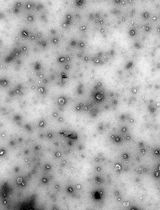

We previously used ginger-derived lipid nanoparticles (GDNPs) for orally delivering CD98 siRNA (Zhang et al., 2017) and 6-shogaol (Yang et al., 2021) to treat ulcerative colitis. These studies suggested that GDNPs could overcome the challenges of oral drug delivery. Further, we found that monogalactosyl-diacylglycerol (MGDG), digalactosyl-diacylglycerol (DGDG), and phosphatidic acid (PA) constitute more than 90% of the total lipids of GDNPs (Zhang et al., 2016; Zhang et al., 2017). In this protocol, we will describe how to use these three lipids at the same ratios found in the GDNPs in the synthesis of new lipid nanoparticles (nLNPs) to encapsulate IL-22 mRNA. The nLNP-encapsulated mRNA showed its therapeutic efficacy in one of our recently published studies (Sung et al., 2022).